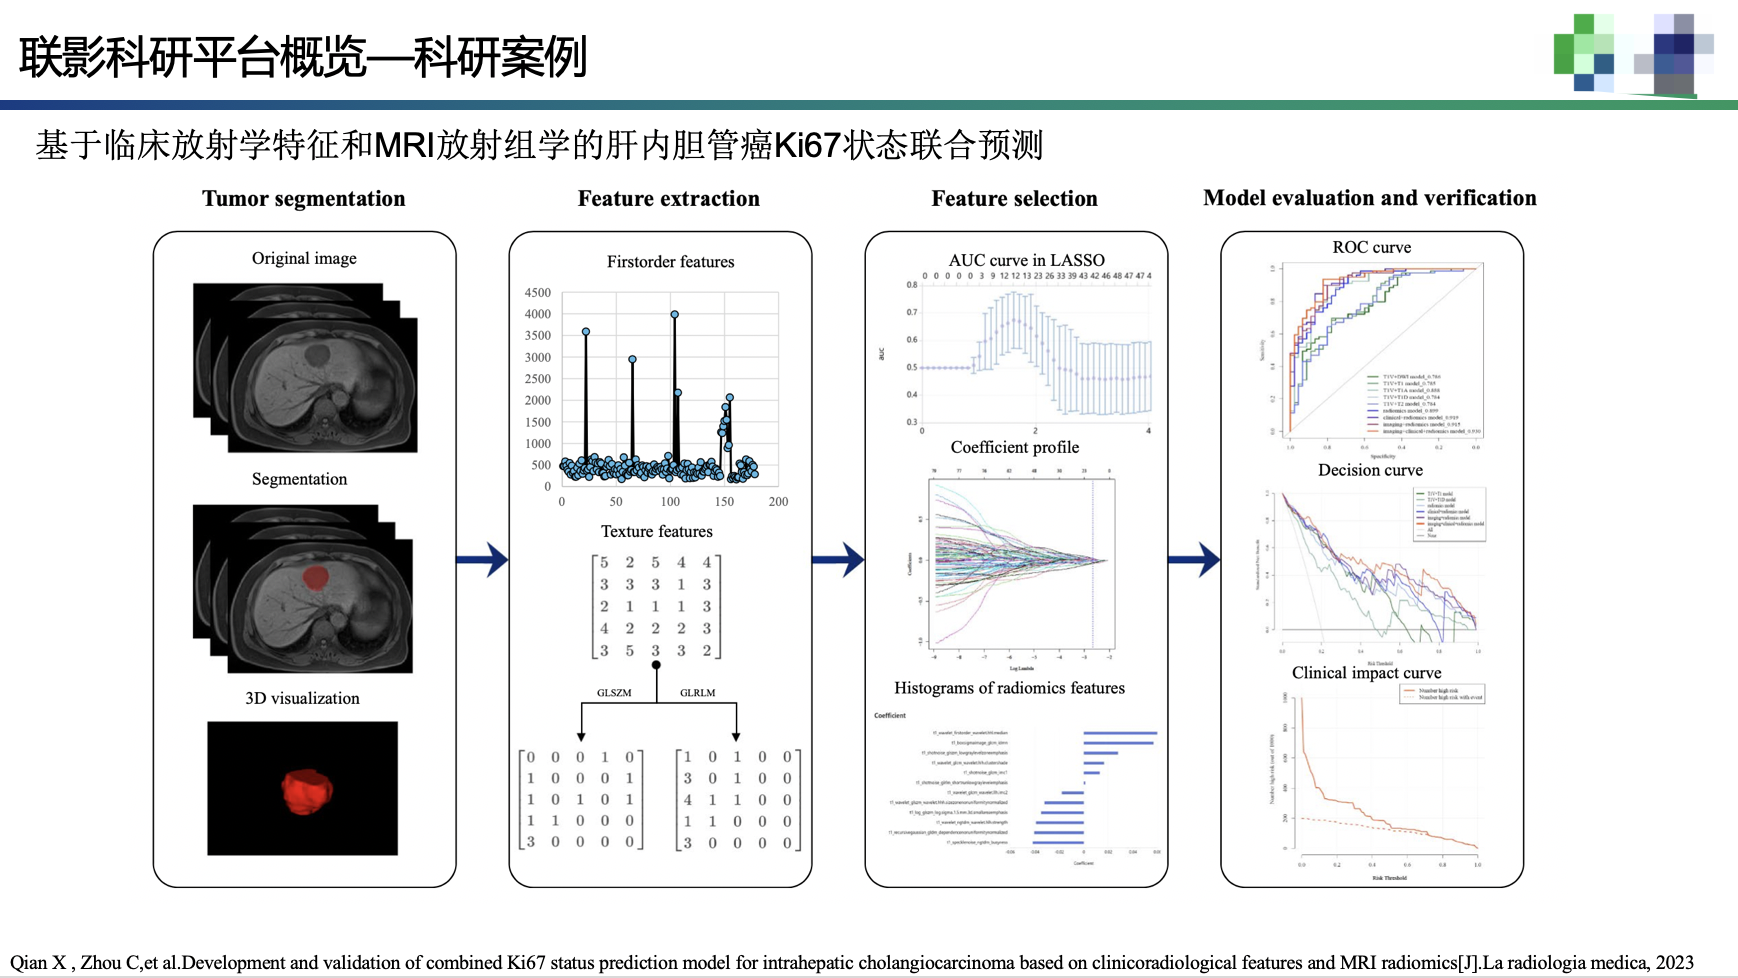

影像组学模块:在组学模块中包含三个子模块:特征提取、特征选择以及机器学习模型的训练。特征提取是在ROI区域提取图像相关的统计特征;特征选择是在特征提取的基础上做相关性分析;机 器学习模型的训练是在特征提取以及特征选择的基础上做相关分类、回归。

最后举一个用该平台发表SCI的论文,感兴趣的可以看一看。